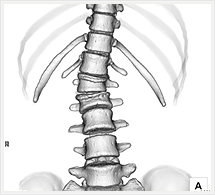

画像紹介

CTでは輪切り像の他にも立体的な画像(3D画像)を作成することもできます。そのためにはより細かくキレイな画像を撮影しなければなりません。当院では64列CTを導入しており、キレイな画像をより細かく撮影することができます。その画像を元に3D画像を作成することによって、より正確な手術のシミュレーションが可能になります。実際に手術をしたときの様子が、手術をする前に画像として見らます。外科系の手術には欠かせない技術となっておりますが、内科系でも血管内手術にも多く利用されております。

当診療放射線技術科では毎日各診療科に対して、その手術に最適な3D画像を提供しております。

以下にその3D画像を一部分紹介します。

脊椎